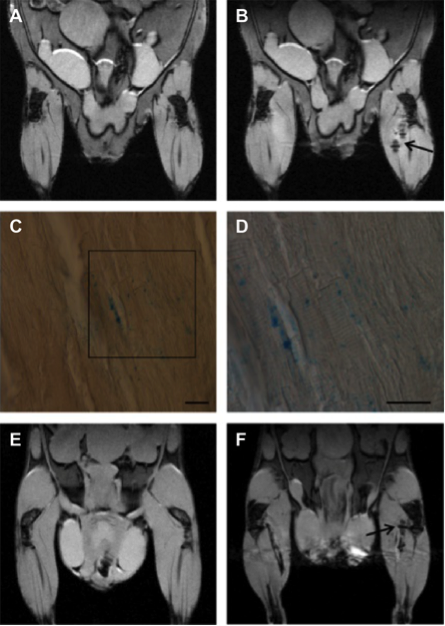

首先,使用超小型超顺磁性氧化铁纳米颗粒(USPIO, 4-6 nm),采用最佳参数来标记的ASCs,在细胞活力、标记效率、铁的含量和磁共振(MR)图像对比度方面进行了研究。然后使用标准分离方法分离标记的ASCs外泌体。外泌体标记的效率通过体外和体内获取MR图像以及通过确定其铁含量进行评估。进行透射电子显微镜图像和组织学分析验证了获得的结果。

通过使用优化的实验参数为ASC标记(200 µg Fe/mL的USPIO孵育72小时),有可能将100%的细胞标记,而它们的细胞活力仍比得上未标记细胞;磁共振图像在体外和体内的检测极限分别为10^2和2.5×10^3的ASCs。透射电子显微镜显示从先前标记的ASCs分离的外泌体保留有标记的纳米颗粒。通过MRI检测外泌体的极限在体外和体内分别为3 µg和5 µg。

USPIO标记外泌体的体内磁共振成像